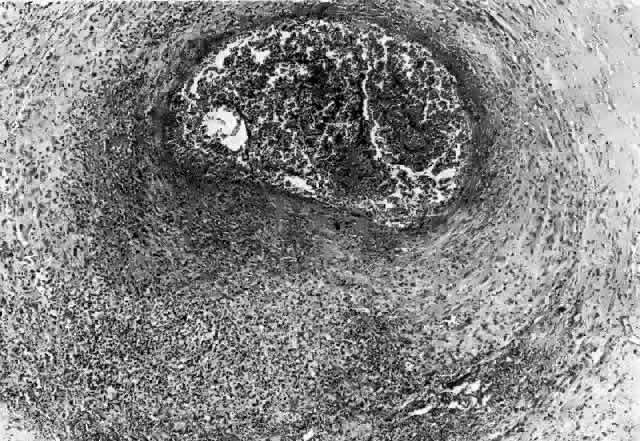

In general, idiopathic orbital inflammation is polymorphic (Figs. 5 AND 6).3,6,7,33,87,88 The cellular response seen in this disease consists of lymphocytes, plasma cells, macrophages, histiocytes, occasional neutrophils and eosinophils, epithelioid cells, and fibroblasts. These are present in varying numbers, depending on the chronicity of the inflammatory process. Intranuclear Dutcher bodies and intracytoplasmic Russell bodies may be present within many of the plasma cells since they actively participate in the inflammatory response. Children tend to have a significant number of eosinophils in their biopsy specimen. Lipogranulomatous inflammation with fat necrosis may also be present. However, the presence of noncaseating granulomas is relatively uncommon.89 This is often associated with foreign body giant cells that are responding to the release of lipid. Perivascular lymphocytic cuffing and capillary proliferation are quite common.3 Occasionally, lymphoid follicles may also be seen.

Fig. 6. Histopathologic sections demonstrating the various pathologic findings associated with idiopathic orbital inflammation. Most commonly these include lymphoid follicles, granulomas, collagen deposition, and a diffuse mixed inflammatory cell infiltrate. The normal tissue architecture is frequently disrupted by these changes. A. Many lymphoid follicles are scattered throughout orbital tissue (H&E, × 63). B. Cells of follicular center are lighter and larger than mantle of mature lymphocytes that surround the germinal zone (H&E, ×160). C. Lacrimal gland elements have undergone atrophy in advanced example of idiopathic dacryoadenitis. Fibrosis and lymphocytes have replaced a considerable amount of gland parenchyma (H&E, ×94). D. Myositis in which lymphocytes are loosely aggregated below center and infiltrate between extraocular muscle fibers (H&E, ×160). E. Cuffing of small vessels by mature lymphocytes. Note loose edematous interstitium between disrupted muscle fibers (H&E, ×240). F. Progressive fibrosis of retrobulbar fat (H&E, ×25).